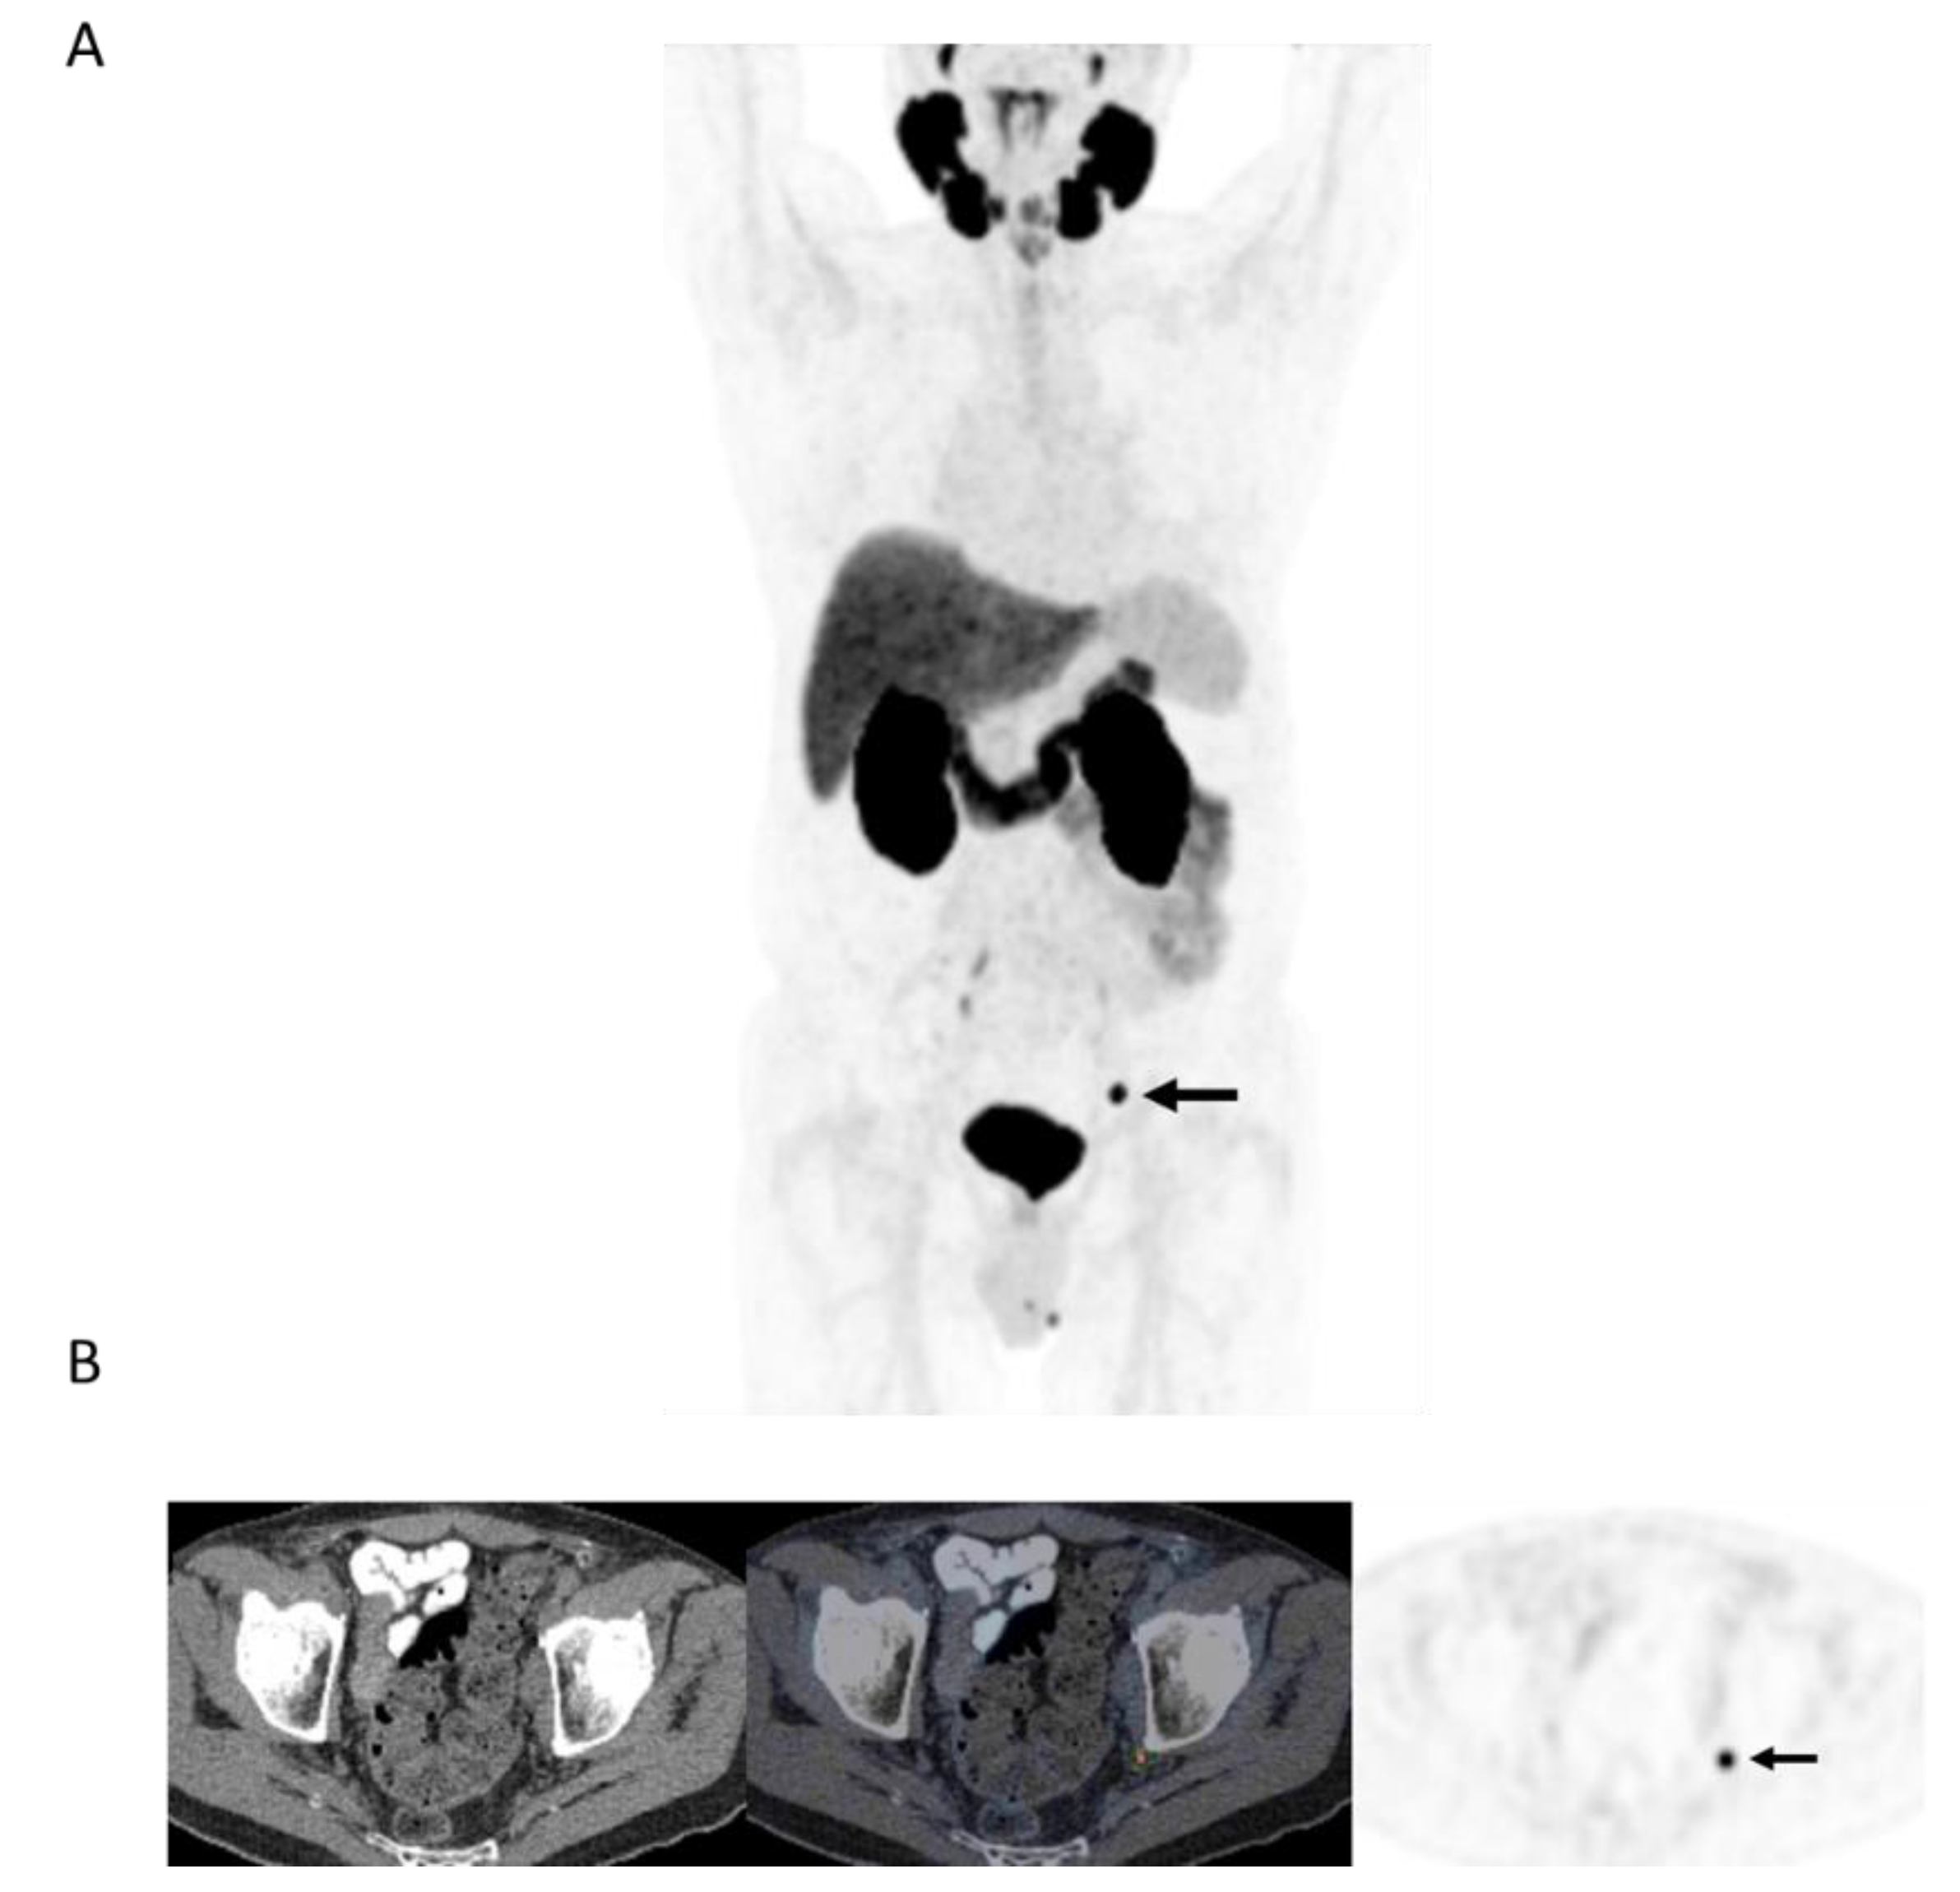

Figure 3.

78-year-old man 4 years after radical prostatectomy for pT3a N0 adenocarcinoma of prostate ISUP Grade Group 3. Now biochemical recurrence (serum PSA = 0.80 ng/mL); PET performed prior to salvage prostate bed radiotherapy. (A) MIP PET image showing solitary focus of abnormal tracer uptake in the pelvis on the left. (B) Axial PET/CT image (CT–left; fused PET/CT–middle; PET–right) shows an intensely 18F-DCFPyL-avid 0.3 cm left pelvic sidewall lymph node (SUVmax = 25.6; PSMA score, 3), in keeping with a metastatic node. After PET, the patient was treated with PET-directed stereotactic radiotherapy with favorable metabolic response (>76% decrease in serum PSA).

Overall, (13/29) 44.8% of patients without extensive metastases on PET were treated with PET-directed focal ablative therapies without systemic therapy (Figure 3). The mean PSA response to focal ablative therapies was 69% (median, 74.5%; range: 35–100). Favorable biochemical response (>50% drop in pre-PET PSA) was observed in 10/13 (76.9%) patients with limited recurrence on PET, and in 3/13 (23.1%), there was complete biochemical response.

Our initial experience with PSMA PET in the workup of patients with biochemical failure after primary therapy for prostate cancer with no definitive metastatic disease on conventional workup has shown PSMA PET positivity in more than 90% of patients, with local recurrence or oligometastatic disease in over half of them. Tumor detection rate in our cohort (with median serum PSA of 3 ng/mL) are in line with those reported in the previous prospective CONDOR trial in which disease detection was 73.3% when serum PSA was <0.5 ng/mL and rose to 96.4% when serum PSA was >5 ng/mL [9]. More than 40% of the patients with limited recurrence were treated with PET-directed ablative therapies to sites of disease without systemic therapy, and the biochemical response was favorable in more than 3 in 4 of them (Figure 3). Overall, in more than 20% of patients in this study (10/47) with biochemical failure and no conventional workup evidence of recurrent disease, PET identified limited recurrence amenable to focal ablative therapies with a favorable biochemical response (>50% drop in serum PSA). In nearly a quarter of patients treated with limited ablative therapies, there was complete biochemical response to therapy. These findings are in line with a prior prospective trial that included 72 patients in whom 38 were treated for oligorecurrent prostate cancer amenable to metastasis-directed therapy. Overall response rate in that study was 60%, including 22% with complete biochemical response at a median follow-up of 15.9 months [10].